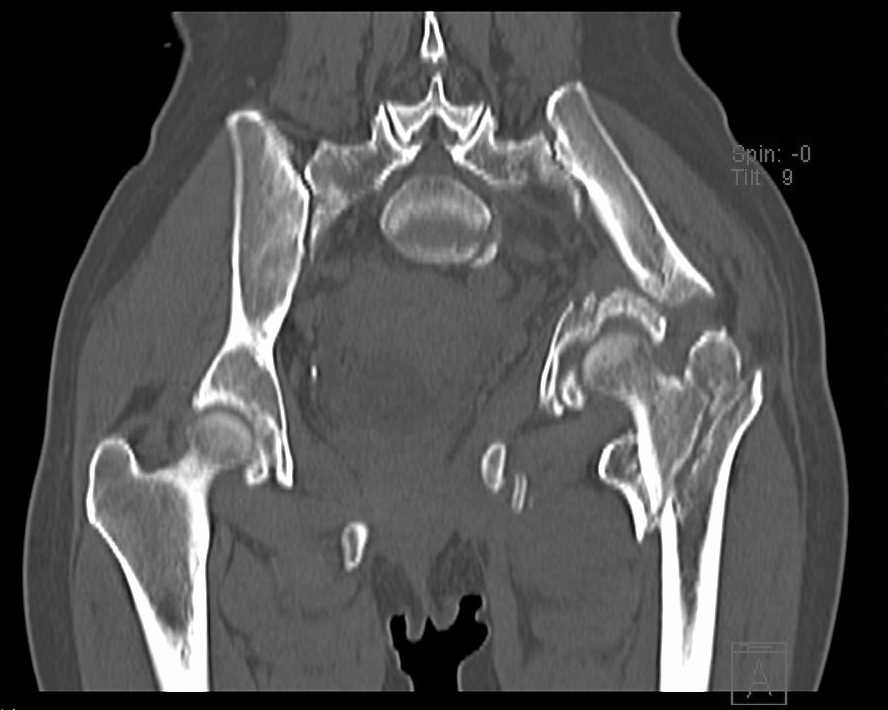

Больная 43 года (промышленный альпинист), 28.07.08 в результате падения с 5 этажа получила политравму: Перелом свода и основания черепа. Вертикально-нестабильное повреждение таза, осложнённое разрывом мочевого пузыря. Чрезвертельный перелом левого бедра. Перелом правой таранной кости, переломовывих правой кубовидной кости. Тупая травма живота, разрыв печени, ушиб почек. Забрюшинная гематома. В день травмы - лапаротомия, ушивание ран печени. Разрыв мочевого пузыря не диагностирован. Течение болезни осложнилось развитием мочевого затёка и обширной пред- и забрюшинной флегмоны, сформировался свищ мочевого пузыря. 19.8.2008 вскрытие, дренировние флегмоны, ревизия мочевого пузыря, обтурация мочевого свища (свищ закрылся в октябре), 1.10.2008 некрэктомия, пластика по Шеде-Лидскому правой кубовидной кости. По результатам КТ диагностирован рак правой почки (диагностическая находка), 8.10.2008 нефрэктомия справа. Переломы велись консервативно. Имеется вертикальное смещение левой половины таза с выраженным отведением крыла (клинически подвижности нет), несросшийся низкий двухколонный перелом левой вертлужной впадины с потерей конгруэнтности, укорочение около5 см, застарелый разрыв лонного сочленения, неправильно сросшиеся переломы обеих ветвей правой лонной кости с укорочением, патологическая подвижность лоно-седалищного фрагмента слева. Правая нижняя конечность неопорна, несмотря на то, что лежа прямую ногу поднимает, ходит на левой ноге (ортопедическая обувь) с костылями, справа тазобедренный ортез. Седалищные нервы работают.Урологи отпустили больную на 6 мес.

Мучаемся мыслями - как все это заставить ходить.Возможно ли первичное протезирование если просто синтезировать лонное сочленение с цементом и ванкомицином? Если делать большую реконструкцию, то с чего начать? Изрубить крыло и заполнить дефекты? Перерубить боковую массу и попытаться развернуть крыло обратно? Ждать год после закрытия свищей?